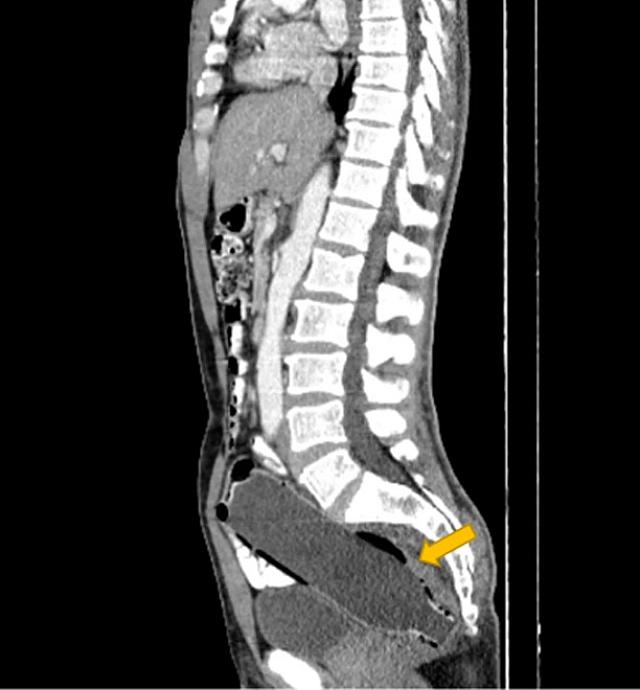

Ένας παντρεμένος άνδρας από το Ιράν αναρρώνει αφού οι γιατροί αφαίρεσαν ένα μπουκάλι νερό από το ορθό του. Το αντικείμενο ανακαλύφθηκε αφού ο 50χρονος έφτασε στο νοσοκομείο με τη σύζυγό του, η οποία ανησύχησε μόλις σταμάτησε να τρώει και άρχισε να υποφέρει από κοιλιακούς πόνους και δυσκοιλιότητα.

Ο άνδρας συνέχισε να κρύβει με επιτυχία το οδυνηρό μυστικό του, μέχρι που αποκαλύφθηκε στους γιατρούς μέσω αξονικής τομογραφίας.

Σύμφωνα με ένα άρθρο στο Clinical Case Reports Journal, ο άνδρας απέφυγε να αναφέρει ότι είχε τοποθετήσει το αντικείμενο μόνος του, λόγω «αμηχανίας» και «φόβου για τη γυναίκα του».

Όταν όμως ήρθε η ώρα να γίνει αυτό, το αντικείμενο παγιδεύτηκε στο παχύ έντερο του άνδρα. Οι γιατροί στο νοσοκομείο Imam Khomeini στο Sari δεν ανέφεραν γιατί ακριβώς το μπουκάλι κόλλησε εκεί, αλλά είπαν ότι η σεξουαλική ικανοποίηση κρύβεται συνήθως πίσω από τέτοιου είδους καταστάσεις. Ο άνδρας ήταν επίσης γνωστό ότι είχε ιστορικό κατάθλιψης, σύμφωνα με το Clinical Case Reports.

Έκανε επείγουσα χειρουργική επέμβαση για την αφαίρεση του μπουκαλιού. Οι χειρουργοί κατάφεραν να τραβήξουν αργά το μπουκάλι προς τα έξω χωρίς να προκαλέσουν βλάβη στο έντερο.

Η μελέτη αναφέρει ότι είχε εισαγάγει το μπουκάλι με το κάτω μέρος να μπαίνει πρώτο, προκειμένου να χρησιμοποιήσει το επάνω μέρος ως λαβή για να το τραβήξει έξω.